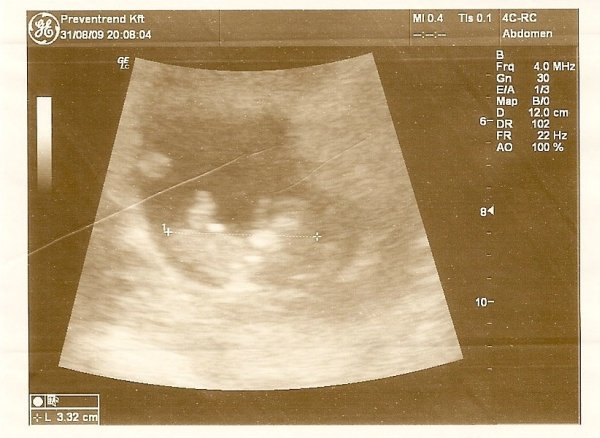

Na hát tegnap voltunk UH-n. Minden Ok!!! :) 34,5 mm a CRL.

Először csak nézegettük, meg a szívhangját hallgattuk, aztán a végén beindult a Babó. Úgy el kezdett ficánkolni, meg boxolni...apjával csak ámultunk, meg könnyeztünk. Szuper volt látni!

Dokival beszélgettünk a Down szűrésről (35 fölött). Ő javasolja a magzatvízvételt. Állítólag ilyen korban már kiegyenlítődik a százalék a vetélés és a beteg baba között. Megoldás lehet a vérvétel előbb és ha esetleg az olyan eredményt mutat, akkor a szúrás. Ezt még át kell gondolni nagyon. (A szúrás TB támogatott állítólag)

Ja meg azt mondta, hogy a vérvétel ugyan 95%-os, de az csak valószínűsít, míg a szúrás 100%-os és biztosat mond. Hááát? Nem tudom mit válasszak....

Itt egy kép a Babóról...aki most egy kicsit medvebocs kinézetű :)

(Persze a szkennelés utáni minőségről ne is beszéljünk)

Moncsi, a kis medvebocs szembe fordul velünk ugye? És már 34,5mm :shock: nő, mint a gomba :lol: :lol:

Medvebocsi tényleg szembenézett. Arccal volt felénk legtöbbet.

Döbbenet tényleg ahogy változik, nő éshogy ott ficánkol a pocakban.